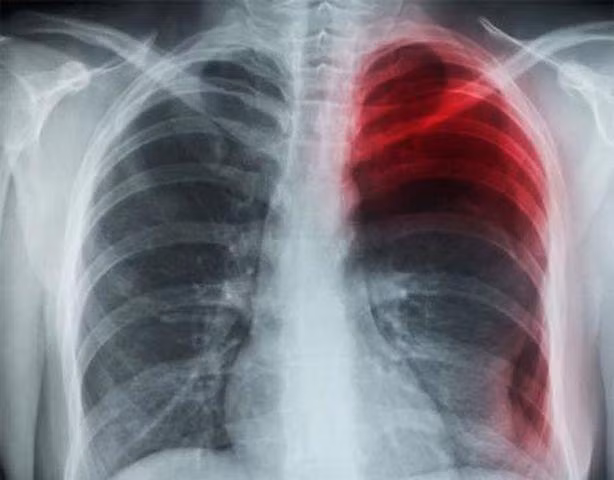

Sau khi kiểm tra sơ bộ, chụp CT, bác sĩ Lý Hiểu Quan, Phó Khoa Hồi sức đã chẩn đoán Tiểu Lý bị tràn khí màng phổi tự phát. Bác sĩ còn phát hiện Tiểu Lý có triệu chứng chảy máu và thủng phổi bên phải.

Tràn khí màng phổi tự phát là tình trạng khí thoát ra từ nhu mô phổi vào khoang màng phổi qua phế nang bị tổn thương mà không do nguyên nhân là lực tác động từ bên ngoài (chấn thương hoặc vết thương).

Bình thường trong khoang màng phổi không có khí và tạo nên áp lực âm, điều đó giúp cho phổi nở để thực hiện chức năng trao đổi khí. Khi có tràn khí vào khoang màng phổi, phổi sẽ bị ép lại, không thể trao đổi khí, gây nguy hiểm đến tính mạng.